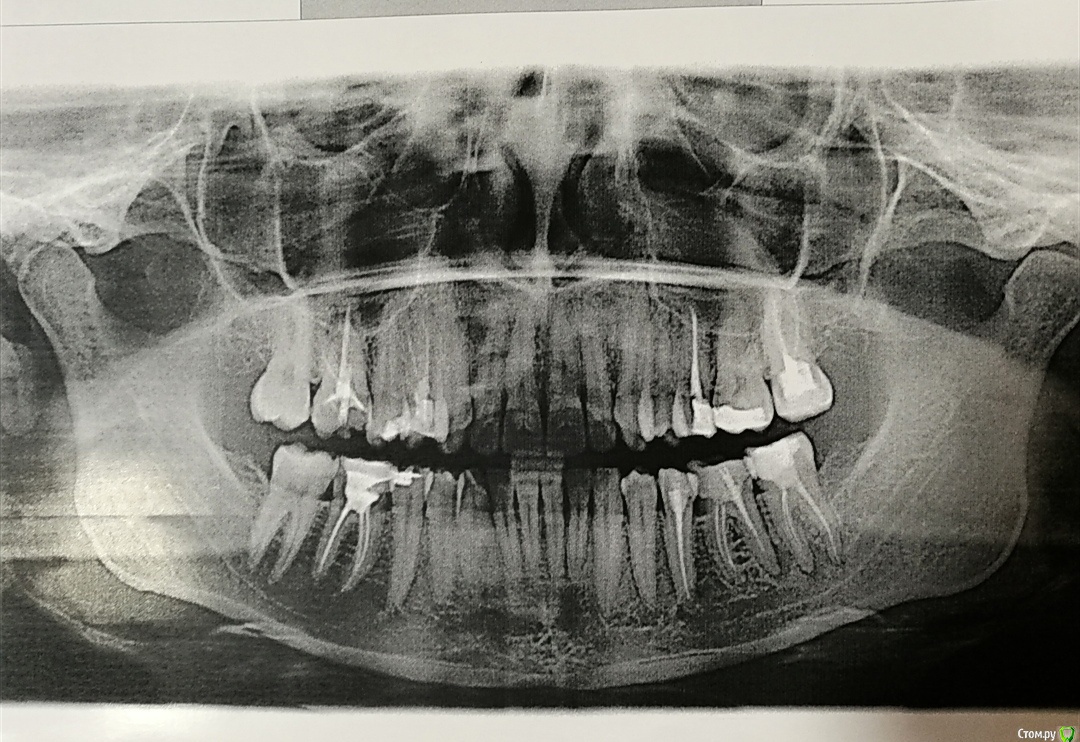

Юлия Китова Опубликовано 28 августа, 2019 Поделиться Опубликовано 28 августа, 2019 (изменено) Здравствуйте! 1. У меня периодонтит 6 и 7 зубов слева снизу. Я хотела удалить 6 зуб, тк он достаточно сильно разрушен, остались две боковые стенки, на одной из которых кариес, как я понимаю ее придется полностью убрать. 7ку пролечить периодонтит и поставить мост. Но ортопед меня отговорил, сказав, что можно пролечить 6ку, установить металлическую вкладку и закрыть коронкой. Понимаю, сложно судить не видя зуб, но я бы хотела узнать, если в дальнейшем, что то пойдёт не так,не возникнет ли проблем с его удалением? Ведь стенок не будет, как удаляют такие зубы? Может быть его сразу удалить. Не хочу чтобы разрезали десну и еще к тому же один стоматолог сказала , что при извлечении штифта зуб может расколоться.2. Ортопед предположил,что был пропущен канал в зубе из за этого развился периодонтит, тк на старом снимке зуб был запломбирован вроде хорошо. Смогут ли этот канал увидеть и пролечить без микроскопа? В нашем городе нету в стоматологиях таких приборов. Может быть в таком случае сделать 3д снимок зубов? Покажет ли он пропущенный канал в зубе? 3. Препарат "Каласепт" тот которым будут пролечивать каналы, подскажите хороший ли это препарат? 4. Страшно ли если периодонтит появится в зубах сверху,ведь там гайморовы пазухи? Как этого не допустить,я похоже понимаю. Нужно закрывать из коронками. Но скажите, можно ли закрыть один зуб коронкой? Не трогать рядом стоящие, которые живые. 5. Почему в бесплатной поликлинике, когда я пришла на приём и хотела чтобы запломбировали зуб на котором кариозное пятно, меня спросили "болит ли зуб? на что я ответила нет. Тогда зачем его сверлить ?" Это правильная тактика? Или это не правильно и почему?Большое спасибо за ответы!) Изменено 28 августа, 2019 пользователем Юлия Китова Ссылка на комментарий